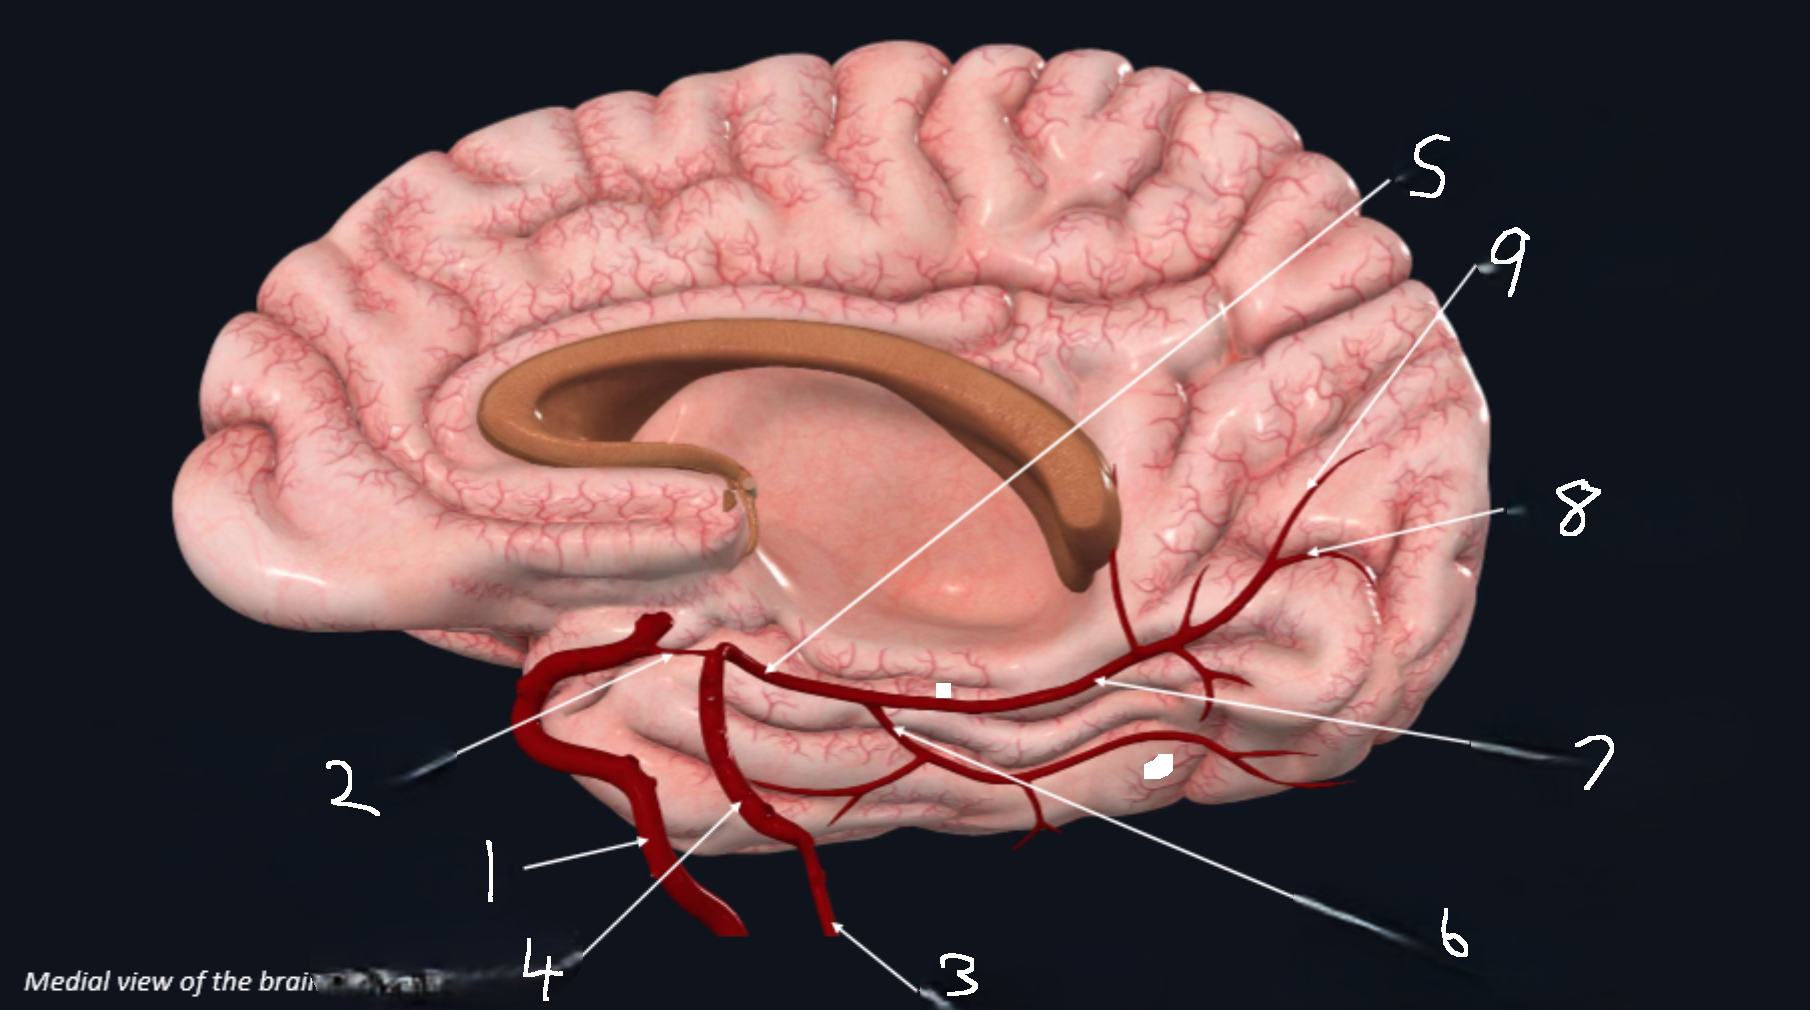

What is 1?

internal carotid artery

What is 2?

anterior cerebral artery

What is 3?

frontopolar artery

What is 4?

pericallosal artery

What is 5?

callosomarginal artery

What is 6?

corpus callosum